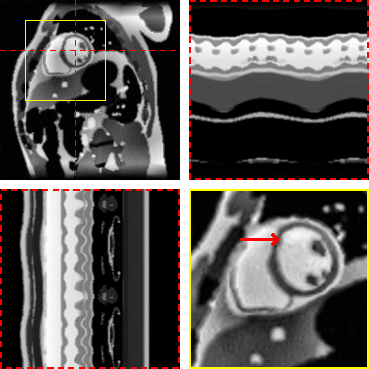

Figure 3: Exemplary MRXCAT phantom reconstructions. Each sub-figure illustrates an end-diastolic frame, temporal profiles, and a close-up on the heart. Red arrows show an area with an artifact in LR-DIP that is suppressed in M-DIP.

The results of the phantom study are given in Table 2. SSIM, PSNR, and NRMSE were computed on the full cine movies, on a region of interest (ROI) around the heart, and on temporal profiles through the center of the heart. M-DIP achieved the best scores in all metrics. The results of M-DIP and LR-DIP are additionally illustrated in Figure 2, and Student’s t-tests were performed to evaluate them for statistical significance. All indicated p𝑝pitalic_p-values are significant (α=0.05𝛼0.05\alpha=0.05italic_α = 0.05) after correction for multiple comparisons using the Holm-Bonferroni method. Reconstruction time was approximately 40 min for M-DIP and 70 min for LR-DIP. Exemplary reconstructions of one phantom are illustrated in Figure 3.

(a) Ground truth

Refer to caption

(b) M-DIP

(c) LR-DIP

(d) L+S